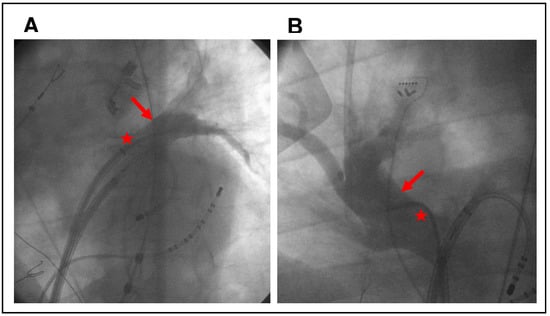

2.2. Pulmonary Vein Angiography